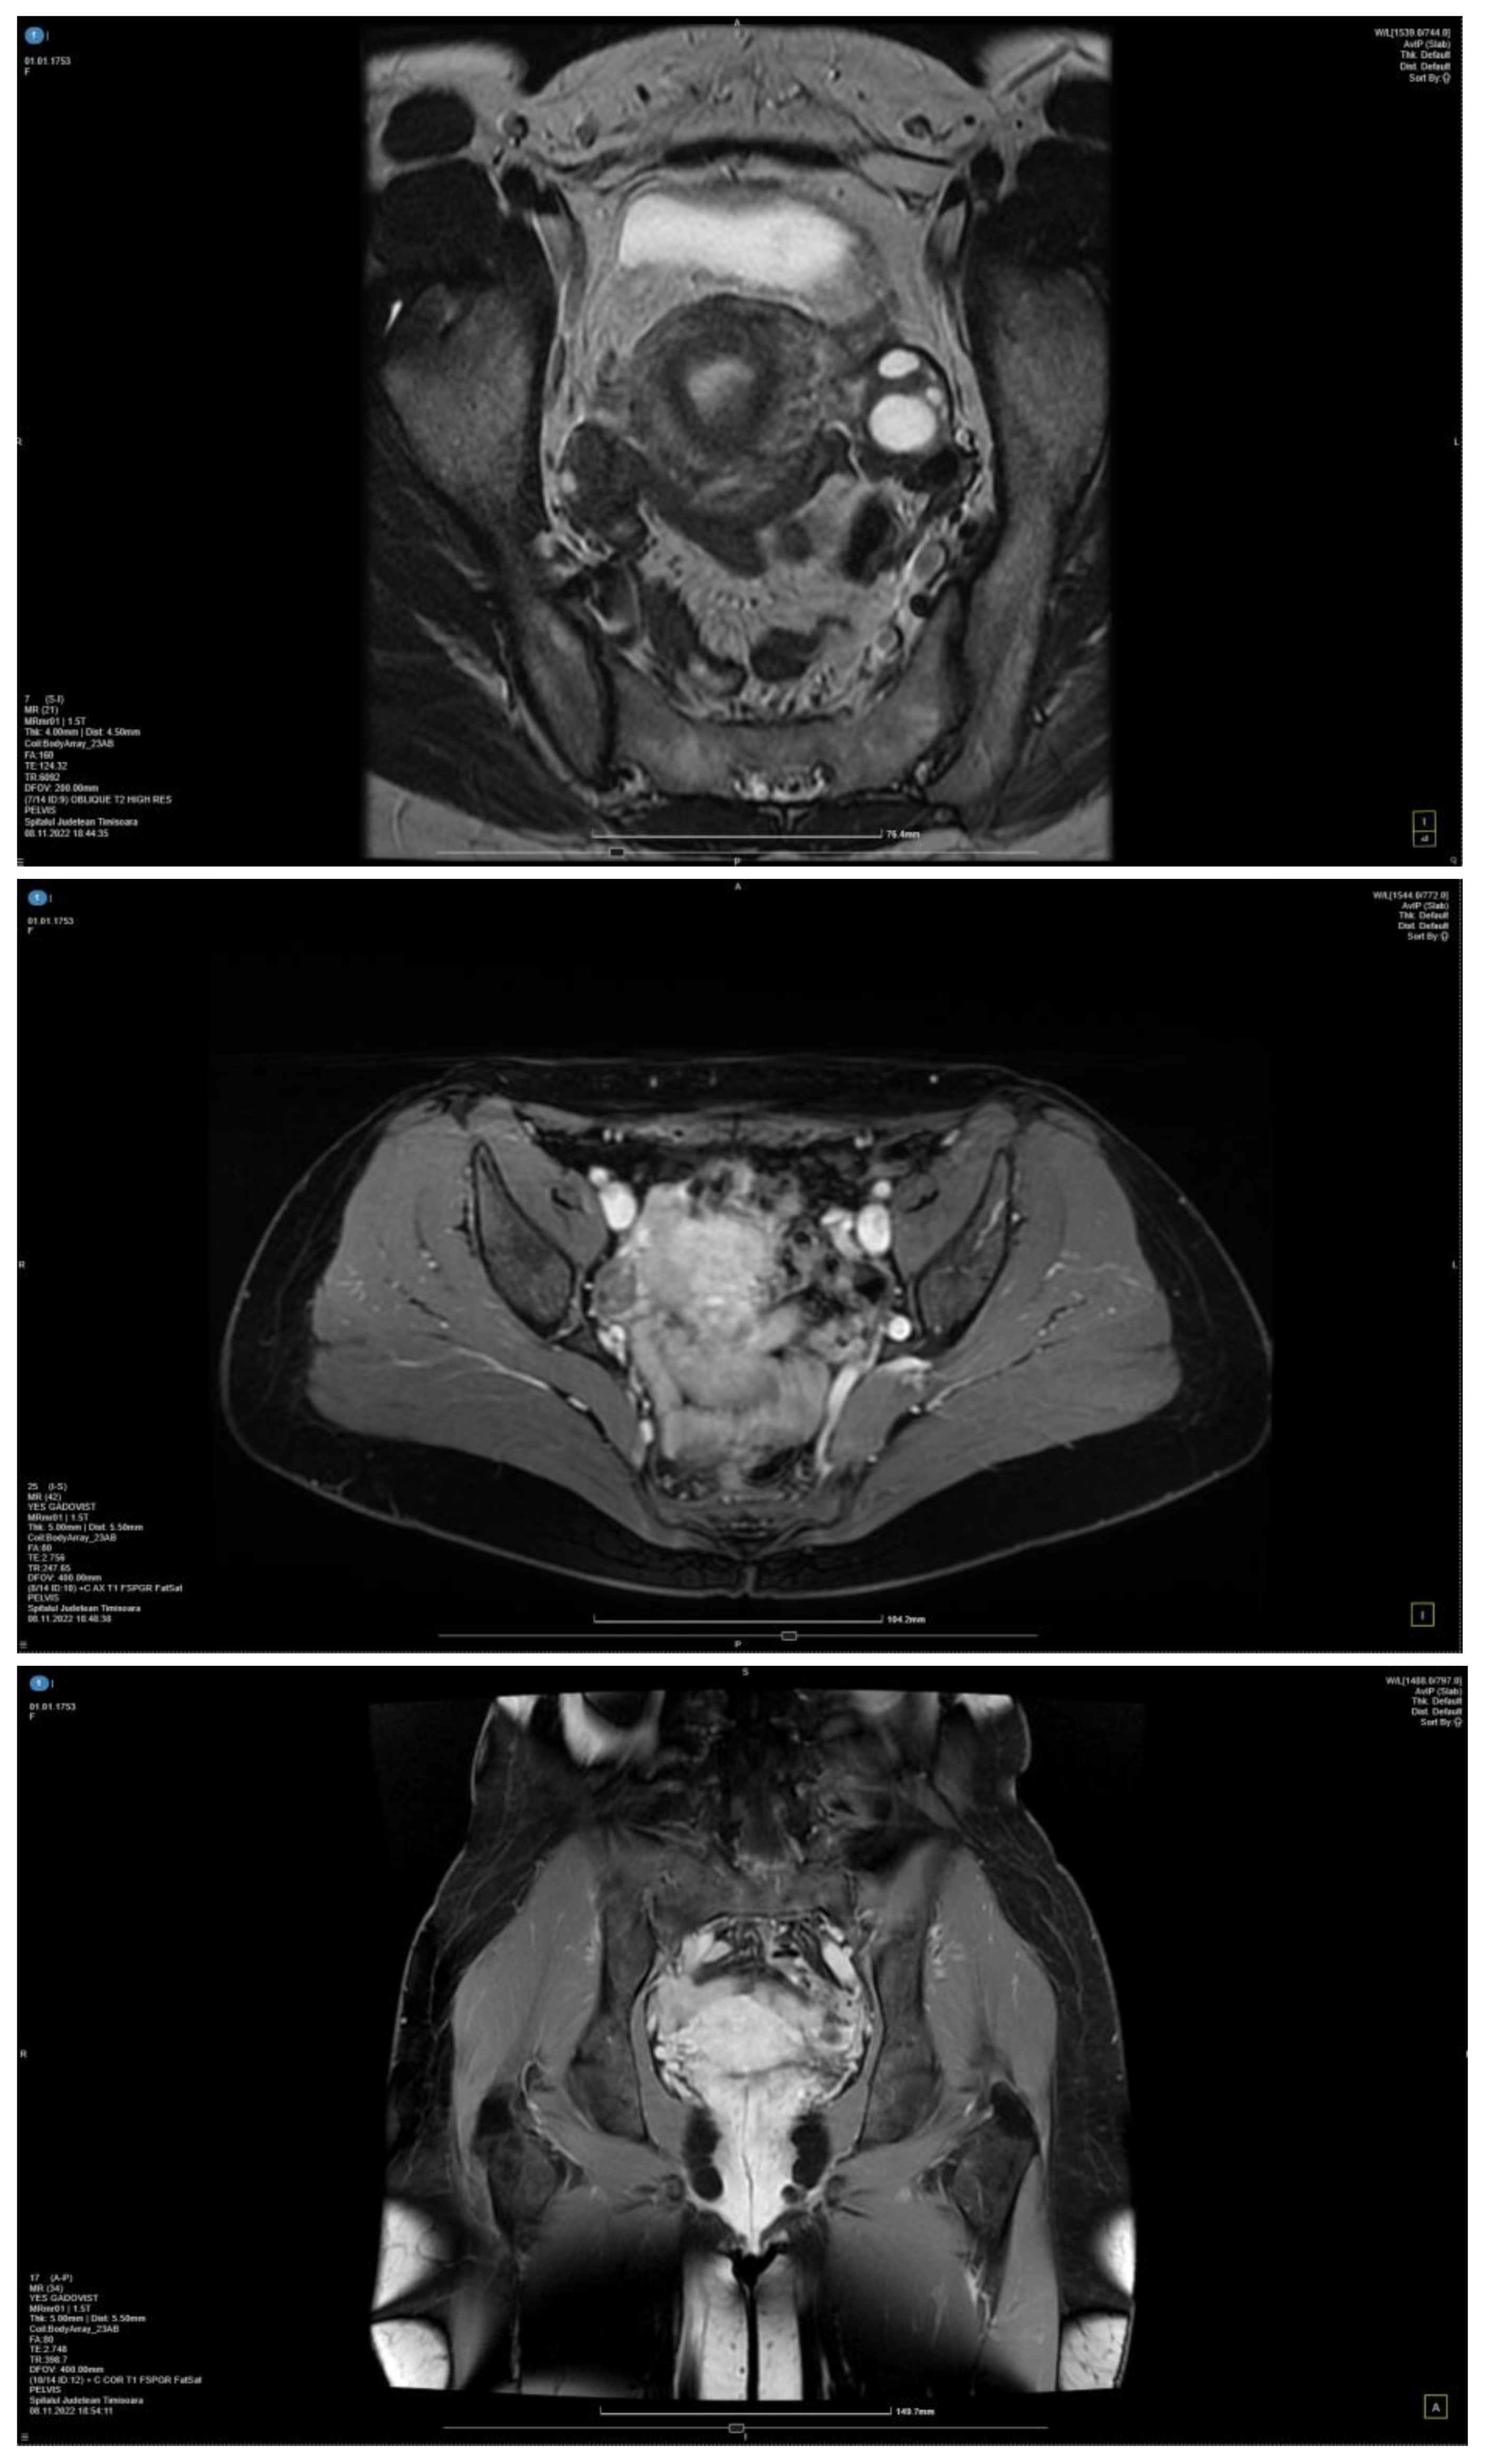

The MRI exam using contrast material revealed a thin blade of free intrapelvic fluid (infracentimetric) at the level of the posterior recess, which, in a physiological context, is as follows: a few bilateral, millimetric, functional-looking ovarian cysts ≤5 mm (follicular cysts); parauterine vasculature with dilated (about 7 mm), tortuous, arcuate, T2 hyperintense and T1 flow voids appearance; and the appearance of simple Naboth cyst with dimensions of 4/2 mm (Figure 3). The diagnosis of pelvic venous congestion syndrome due to left ovarian vein insufficiency was established.

Figure 3.

MRI with contrast material in 2 different planes: axial (I) and coronal (A) planes.